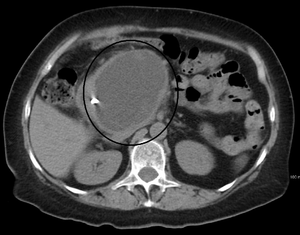

A pancreatic pseudocyst as seen on CT

A pancreatic pseudocyst is a circumscribed collection of fluid rich in pancreatic enzymes, blood, and necrotic tissue, typically located in the lesser sac of the abdomen. Pancreatic pseudocysts are usually complications of pancreatitis,[1] although in children they frequently occur following abdominal trauma. Pancreatic pseudocysts account for approximately 75% of all pancreatic masses.[2]